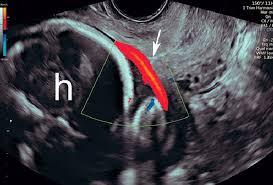

● Transvaginal technique + low-velocity Doppler tips

● Distinguishing fetal vs maternal vessels